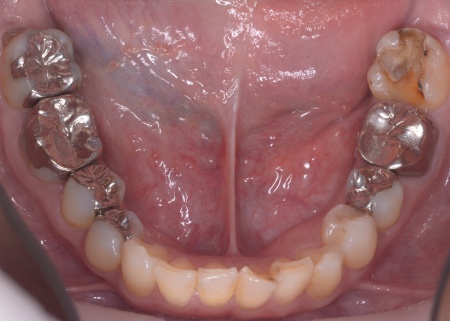

| カウンセリング | 拝見したところ、上前歯が大きく前に出ている上顎前突であり、上下の前歯が噛み合わずに口を閉じても前歯同士が接触しない「開咬(かいこう)」の状態でした。 レントゲン撮影をして詳しく調べた結果、歯の位置だけでなく、骨格的な問題があることが分かりました。 また、前歯で食べ物をうまく噛み切ることができないため、奥歯にも強い負担がかかっているだけでなく、このまま放置すると、奥歯がすり減ったり痛みが生じたりするリスクもあります。 以上のことから、噛み合わせを改善する治療が必要だと診断しました。 |

患者様の場合、骨格的な上顎前突が噛み合わせを乱している主な原因であることから、矯正治療では前歯を後方へ大きく動かすためのスペースを確保する必要があります。 そのため、今回は以下2つの方法を提案しました。 ①抜歯後、アンカースクリューを用いたワイヤー矯正 メリット:骨格的な上顎前突に対応しやすく、前歯を大きく後方へ動かすことができる ②取り外し可能な装置を使用するマウスピース矯正 メリット:装置が透明で目立ちにくく、取り外しができる 以上のメリットとデメリットを丁寧にお伝えしたところ、患者様は①のアンカースクリューを用いたワイヤー矯正を選択されました。 まず、上顎の左右奥歯を抜き、前歯を後方に動かすためのスペースを確保します。 治療の結果、前歯が正しく噛み合うようになり、横顔のバランスも整いました。 矯正治療終了後は、歯が元の場所に戻らないよう上下前歯に保定装置(リテーナー)を装着し、治療を終了しています。 |